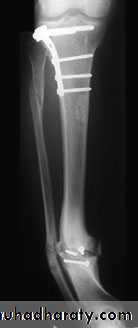

1-Closed intramedullary nailing This is the method of choice for internal fixation. The fracture is reduced under x-ray control and image intensification. For diaphyseal fractures, union can be expected in over 95 per cent of cases. However, the method is less suitable for fractures near the bone ends.

2-Plate fixation is best for metaphyseal fractures that are unsuitable for nailing. It is also sometimes usedfor unstable tibial shaft fractures in children.

Operative treatment